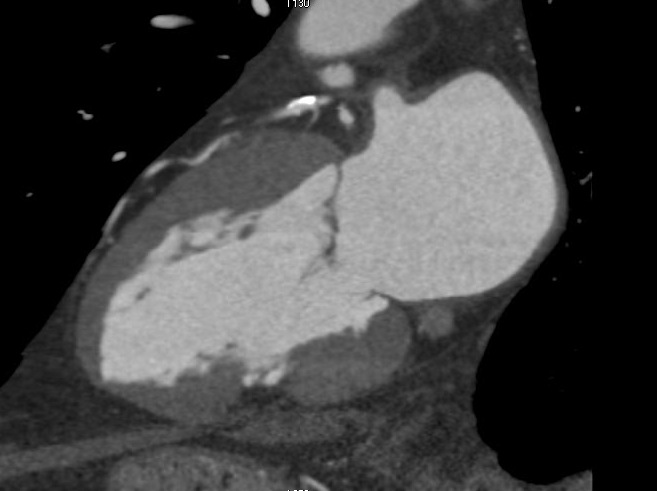

Dans un contexte de récidive d’angor, la ventriculographie retrouve une ectasie infero laterale

Le scanner met tout le monde d’accord, il s’agit d’un pseudo pseudo-anévrisme avec de la paroi, qui est le siège d’une transformation lipomateuse, visible en noir sur le scanner (graisse). Il n’y a donc pas d’indication chirurgicale.